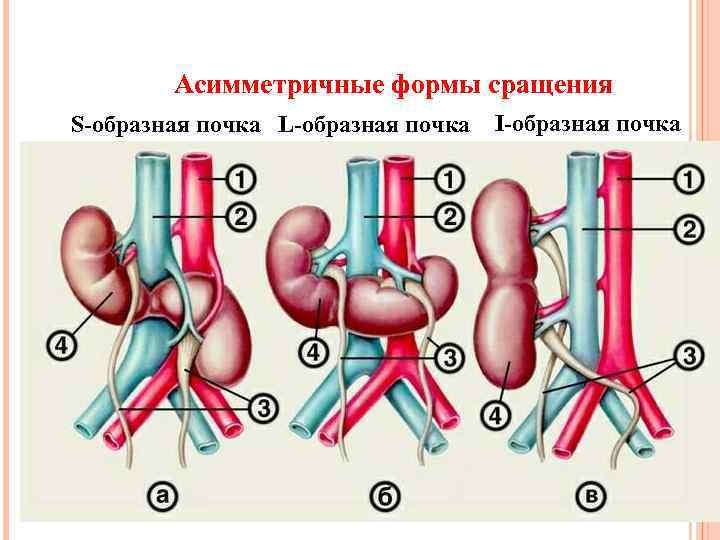

Асимметричные формы сращения S-образная почка L-образная почка I-образная почка

Асимметричные формы сращения S-образная почка L-образная почка I-образная почка